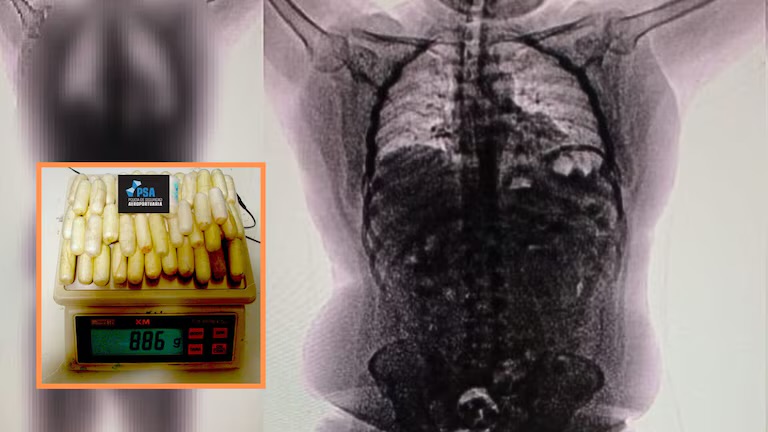

Su nerviosismo también llamó la atención. Fue conducido a una sala de revisión, donde se le practicó una tomografía. La imagen fue el punto de quiebre: una gran cantidad de cuerpos extraños —compatibles con cápsulas— aparecía en su zona abdominal. Inmediatamente, fue trasladado al Hospital de Ezeiza bajo custodia policial, donde comenzó la evacuación de la droga.

Salió de Lima la madrugada del 23 de mayo con una mochila negra, un pasaporte peruano y 90 cápsulas de cocaína escondidas dentro del cuerpo. Diego Edson Morales García, de 29 años, tenía planeado llegar hasta Milán con escala en Buenos Aires y Frankfurt. Pero nunca abordó el último tramo. La sustancia que llevaba en su interior —más de 800 gramos de clorhidrato de cocaína— terminó por delatarlo.